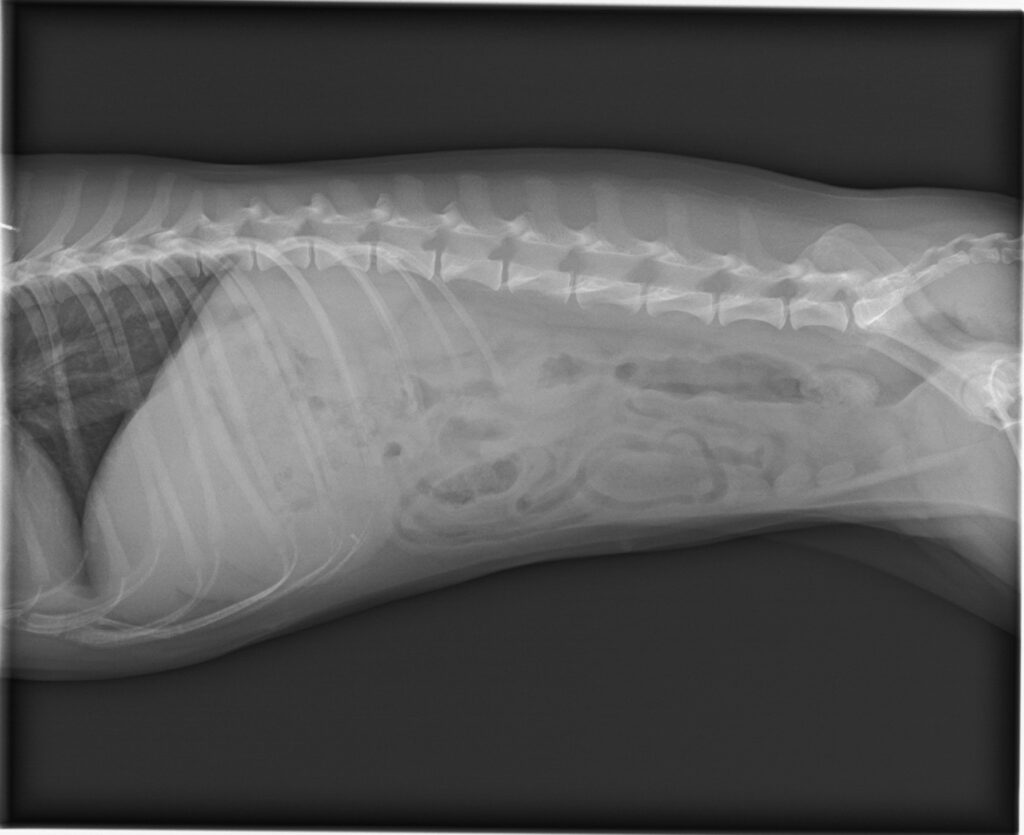

来院時は活動性低下と食欲低下がみられ、嘔吐あるいは嘔吐姿勢を繰り返していました。レントゲン検査・超音波検査で消化管閉塞を強く疑う所見がありました。血液検査などでは著しい循環不全や凝固異常は確認されませんでした。鑑別としては、消化管内異物、腸閉塞、重度の胃腸炎などが挙がります。本症例では閉塞の進行や腸管障害を避けるため、緊急手術としました。

開腹下に消化管を確認したところ、胃から十二指腸にかけて連続するひも状の異物を触知しました。異物は軟性であったため慎重に胃内へ戻し、胃切開によって毛球を摘出しました。胃内には他にも毛球が認められ、あわせて摘出しました。